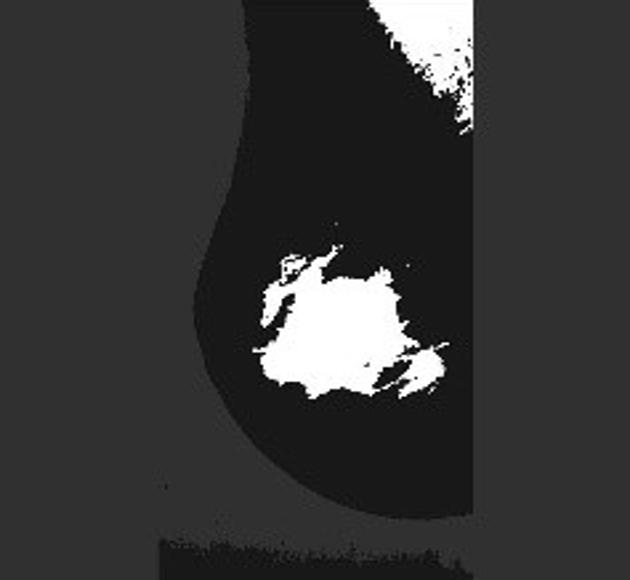

Neural networks require a large number of images as input for the training purposes. Because of limited resources of large dataset availability, the dataset used for this research is mini MIAS dataset [10]. It comprises of total 322 images which are further divided into a number of classes. Original size of each image in the dataset is 10241024. Sample images are shown in Figure 1.

Figure 5 shows a few sample images obtained after segmentation.